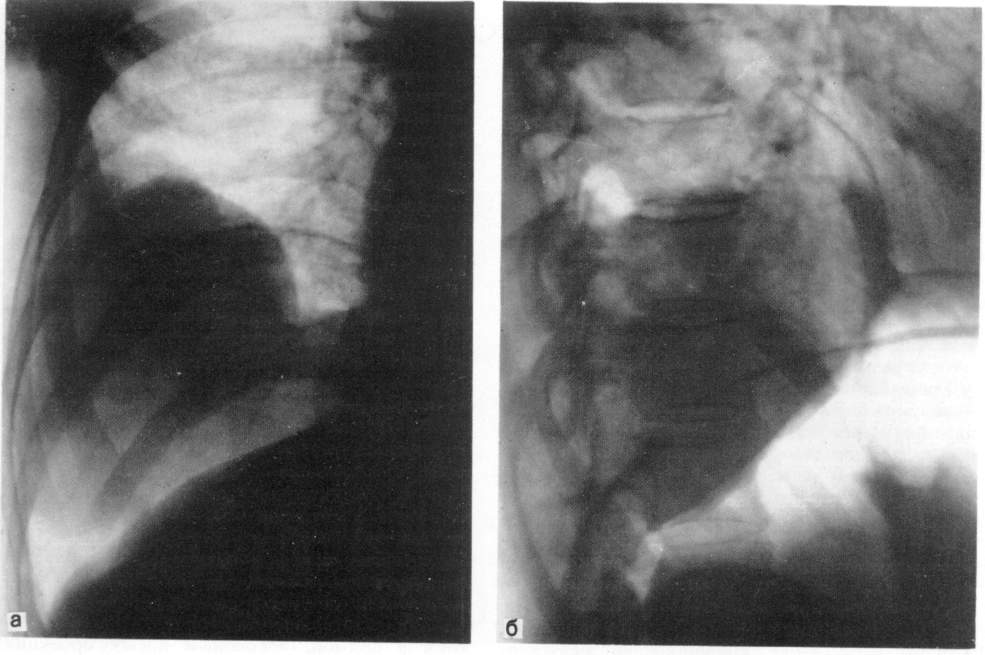

ДИАГНОСТИЧЕСКИЙ ПНЕВМОПЕРИТОНЕУМ

Показанием к введению воздуха или кислорода в брюшную полость с последующим рентгенологическим обследованием являются образования, прилежащие к нижним долям легких и куполу диафрагмы, когда не удается ответить на вопрос: располагаются ли они в легком, исходят из диафрагмы или находятся в поддиафрагмальном пространстве, например в печени (рис. 4).

Рис. 4. Доброкачественная опухоль правого легкого в условиях искусственного пневмоперитонеума.

а — прямая рентгенограмма; б — боковая рентгенограмма.